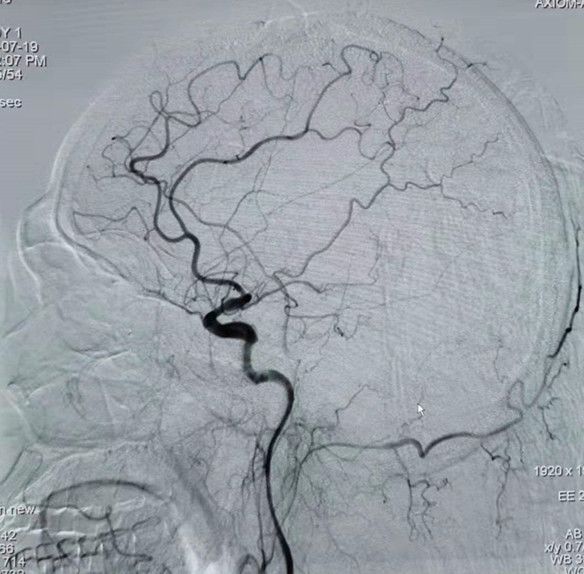

治疗过程

图4 单弯造影管进入左侧颈总动脉后造影:LM1段闭塞